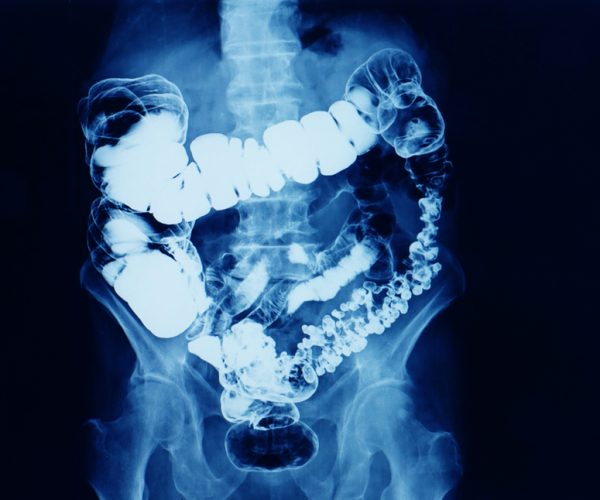

What is a Barium Enema?

A barium enema, also called a lower gastrointestinal (GI) series, is a diagnostic test used to evaluate the colon and rectum for abnormalities. During the procedure, liquid barium sulfate (a contrast dye) is introduced into the colon through the rectum. The barium coats the lining of the intestine, allowing it to be clearly visible on X-ray images. In some cases, air may also be introduced (a double-contrast enema) to improve detail. This test helps detect polyps, diverticula, tumors, strictures, and inflammatory conditions. Although colonoscopy is more commonly used today, barium enema remains useful in specific cases.